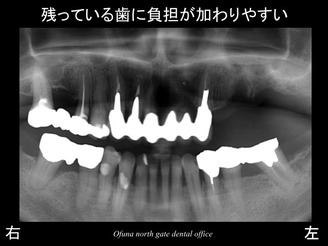

以下のレントゲンは初診時です。

上顎左側の奥歯に問題がありました。

歯肉が腫れ、グラグラとしてきたため、当医院を受診されました。

結論として、上顎左側の奥の2歯は、抜歯と診断しました。

そのため、今回の場合 残っている歯に負担が加わってしまったのです。